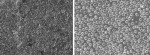

Figure 5 provides an SEM visualization of a dentin surface that had been treated 42 times with S, the desensitizing toothpaste containing potassium nitrate. A particulate residue can be seen on the dentin (Figure 5a). The close-up shows that the particulate residue is present in the entrance to the tubules (Figure 5b).

EDX analysis of the surface indicates the presence of large amounts of silicon dioxide, which almost completely covers the dentin surface in the area evaluated. Because of the coverage, carbon, calcium, and phosphorous peaks from dentin are not seen. It seems that silica coverage is more extensive than apparent in the SEM images.

Table 4 shows that S produces highly variable reductions in dentin flow rate (high standard deviations). After 42 sequential treatments, the average reduction in flow rate was 64.15%, which was similar to that obtained after 40 treatments of dentin with AHECS (57.4%).

Figure 6 provides an SEM of dentin treated with A. A highly mineralized surface deposit is seen on the isolated sealants-treated dentin, and the tubules are blocked (Figure 6a). Also shown is an SEM of the KN-treated dentin (Figure 6b). No mineralization is visible, and the open tubules are clearly visible.

SEMs of the discs treated with IF show mineral deposits on the dentin. In some areas there is complete occlusion of the tubules (Figure 7a); in others the occlusion is significantly less. However, none of the dentin treated with C-2 exhibited visible deposits (Figure 7b), and the tubules remain completely open.